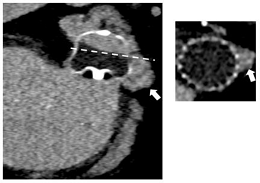

| TEE | CT | |

|---|---|---|

| DEFINITION/METHODS |

|

![]() | ![]() | |

| LIMITATIONS |

| INCIDENCE * | PDL: 26% [24] | LAA Patency: 55% [24] PDL: 57% [24] |